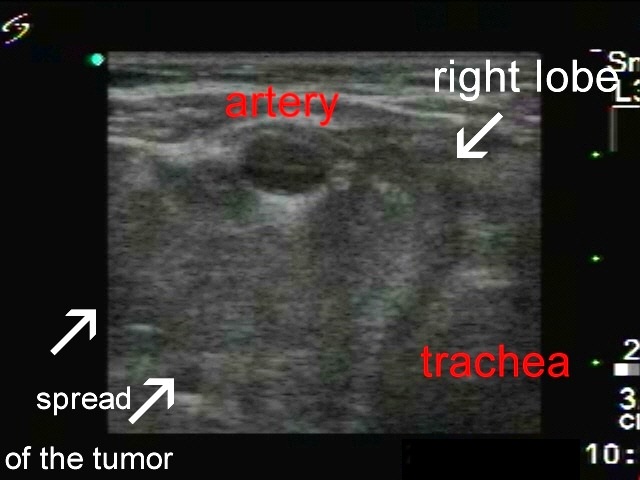

Thyroid cancers - case 1774 (ultrasonographic picture 2b)

Right lobe, transverse view. In the central part of the picture we can see the artery carotid. Medial (right in the image) to the artery is the right thyroid, while the mass dorsal and lateral (left in the image) to the artery corresponds to direct spread of the tumor outside the thyroid.